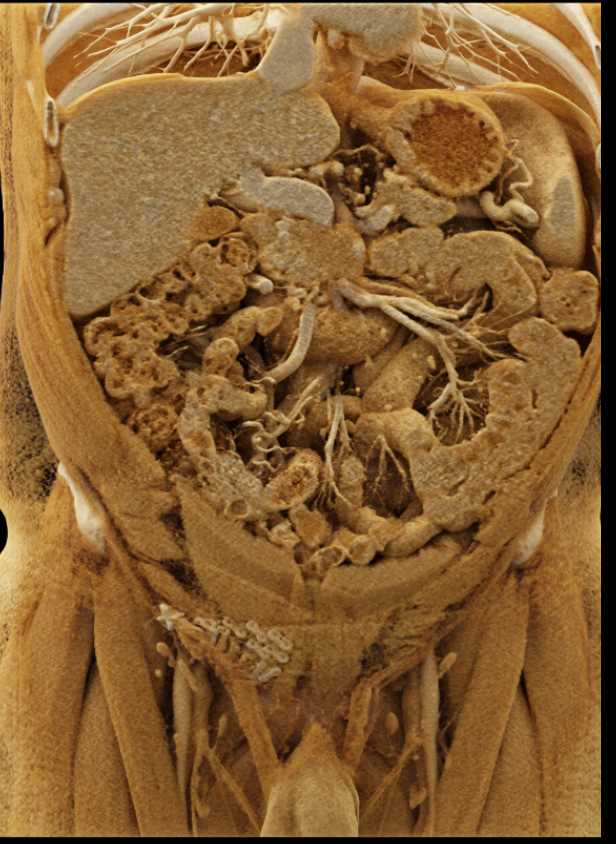

Serous Cystadenoma Head of Pancreas